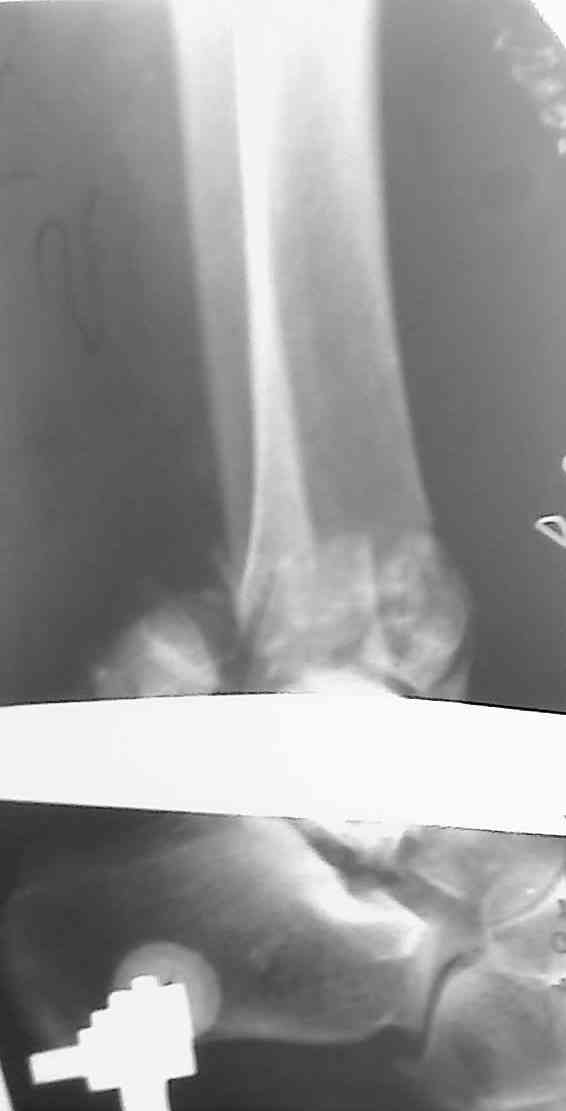

Перелом пилона

Уважаемые коллеги,прошу совета. Девушка, 29 лет, падение с высоты 10 дней назад. Рентгенограммы в приложении, КТ пока не готово, выложу по возможности.

Предполагается ORIF м/берцовой кости 1/3 трубчатой пластиной, дистального конца б/берцовой - винтами + пластиной LCP.

Мнения коллег разошлись по следующим вопросам:1. Какие доступы выбрать, с какого отдела начинать.

2. Облегчит ли работу дистрактор.

3. Потребуется ли костная пластика.